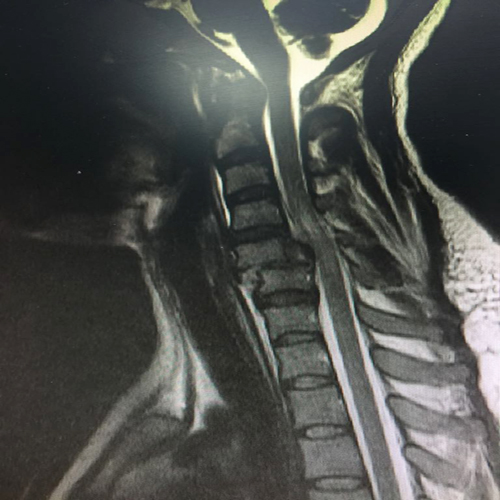

حضرت مريضة سعودية تعاني من كسر وخلع بالفقرات العنقية الخامسة والسادسة وضعف بالأطراف العلوية، وبعد عرض الحالة على الدكتور حازم فريد جراح العمود الفقري حيث قام بإجراء عملية جراحية لإصلاح الخلع وتثبيت الفقرات العنقية بواسطة شريحة ومسامير وبعد الجراحة تماثلت المريضة للشفاء وتحسنت قوة العضلات بفضل الله تعالى وخرجت المريضة بحالة جيدة.